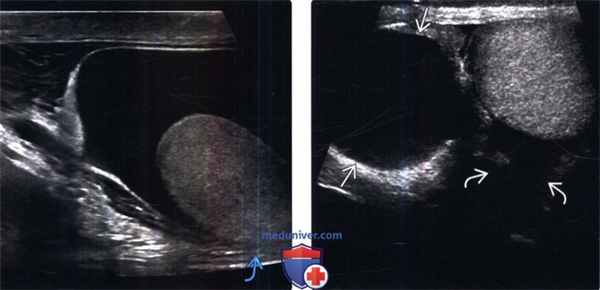

3. УЗИ при гидроцеле:

о Серповидное анэхогенное скопление жидкости, окружающее яичко

о Аваскулярное скопление

о УЗИ

(Слева) На УЗИ мошонки, у мужчины 28 лет с дискомфортом в этой области, определяется простое гидроцеле. Обратите внимание как скопление жидкости окружающее яичко, за исключением «голой» области. Большинство вторичных гидроцеле у этой воз -растной группы возникают вследствие предшествующего эпидидимита.

(Справа) На УЗИ, выполненном мужчине 45 лет с пальпируемым образованием в мошонке слева, определяется крупная киста придатка и небольшое гидроцеле по соседству. Киста смещает яичко в большей степени, чем окружает.